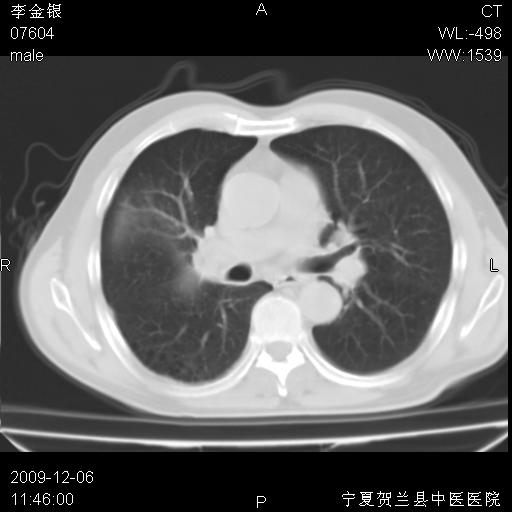

该病人 ,男,62岁,主因咳痰带血两天

考虑右肺中央型占位性病变并阻塞性肺炎.(右肺上叶支气管变窄),建议支纤镜检查.

考虑右肺中心型肺癌伴阻塞性肺炎及右肺门淋巴结转移,建议纤维支气管镜进一步检查。

支气管壁明显增厚 管腔狭窄,腔静脉后多个淋巴肿大,结合年龄病史考虑右肺上叶中央型肺癌并阻塞性肺炎

右肺上叶后段支气管阻塞,右上肺门占位,相应肺段阻塞性肺炎,右肺门有淋巴结肿大。诊断右肺上叶中心型肺癌,阻塞性肺肺炎、右肺门淋巴结转移。

右上叶支气管狭窄,管壁增厚,远端斑片状软组织影,病灶邻近叶间裂,叶间裂无移位。

诊断右肺中央型肺癌。

那个片影应该大部分都是病灶,病灶沿肺段支气管分支生长,后段完全显示不清、闭塞。若为不张应该伴有叶裂的移位,若为炎症应有空气支气管征。

右肺中心型肺癌伴阻塞性肺炎及右肺门与纵膈淋巴结转移很典型,可纤维支气管镜进一步检查

考虑右侧中央型肺癌伴右肺上叶后段阻塞性炎症、肺不张、右肺门和纵隔淋巴结肿大。

右肺上叶中心型肺癌,阻塞性肺炎、右肺门和纵隔淋巴结转移。